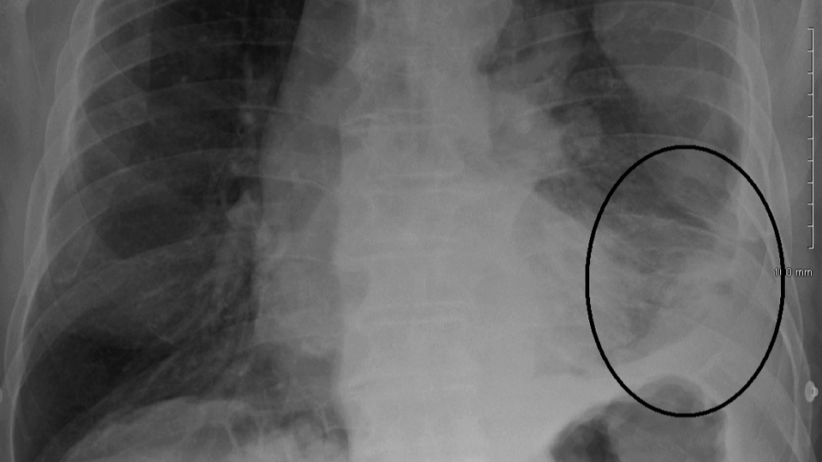

Between 1999 and 2017, Kentucky recorded more than 3,100 asbestos-related deaths, with nearly 580 linked directly to mesothelioma and 237 connected to asbestosis. In the small community of Pike County, there were 38 asbestos-related deaths, further underlining the importance of tracking the at-risk veterans.

Roughly 30 percent of all mesothelioma cases involve veterans, and Kentucky’s veteran population has been hit hard. From those who served on asbestos-laden Navy vessels to those stationed on bases where asbestos was used as a building block for all their infrastructure, countless veterans were exposed. Yet, the VA – which built registries for Agent Orange and burn pits exposure – has never created one for asbestos. A Mesothelioma Registry under the VA and DoD collaboration could finally ensure early screenings, accurate diagnosis, and fair compensation for the affected veterans.